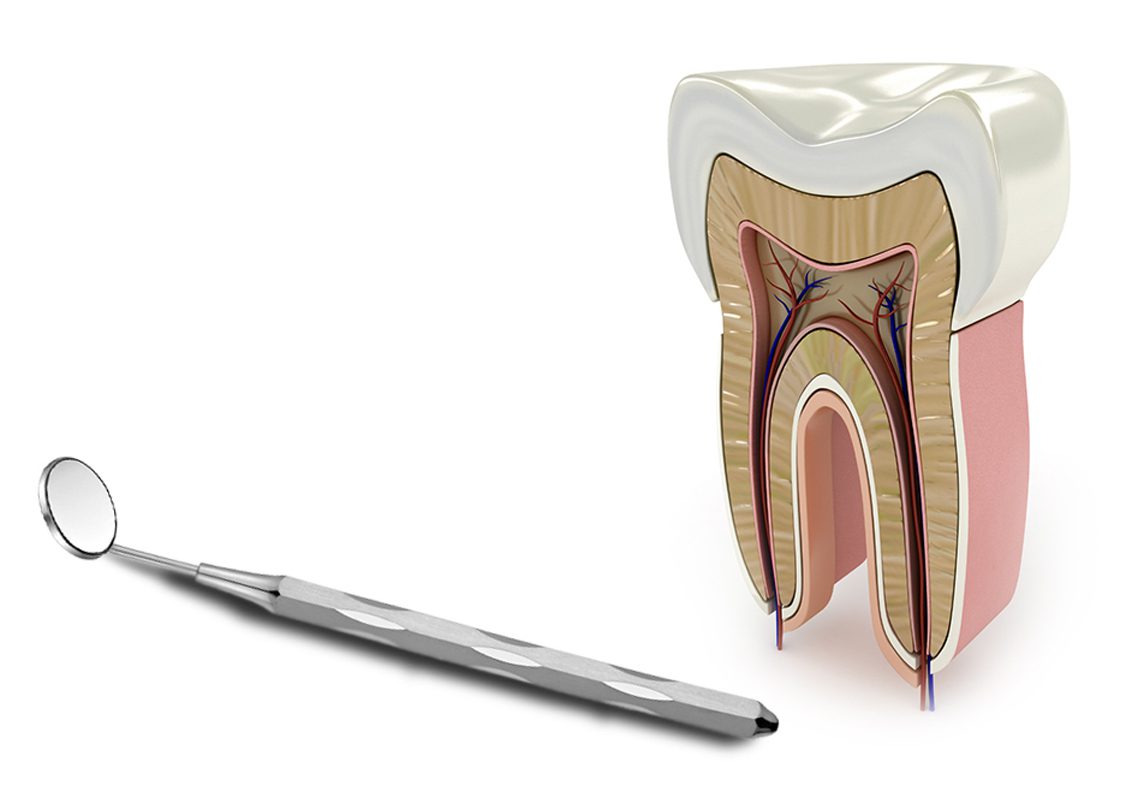

Mikroskop altında kanal tedavisi

Kanal tedavisinde görüş oranının arttırılarak daha detaylı ve kesin neticeler elde edilmesi için büyütme altında çalışılmasını sağlayan mikroskoplardan yararlanılır.